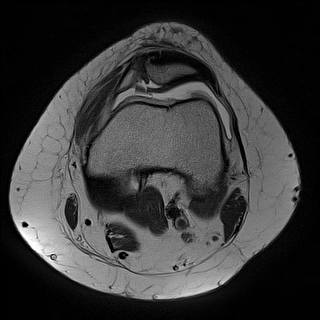

Chấn thương sụn xương khớp gối (Osteochondral Injury, Knee)

16/03/2026